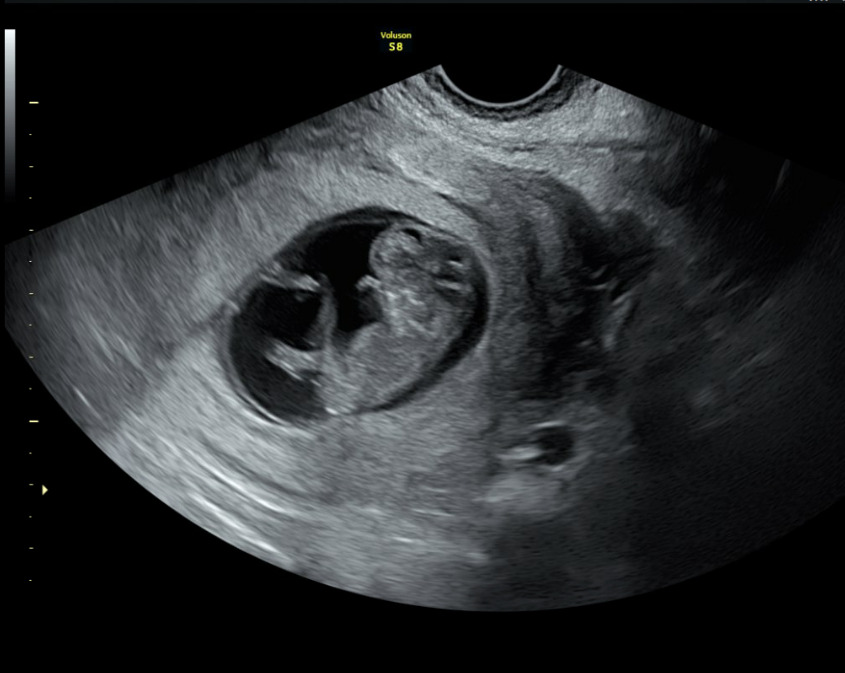

A formal transabdominal and transvaginal ultrasound subsequently revealed a viable intrauterine pregnancy consistent with 10 weeks gestation, confirming the diagnosis of a missed intrauterine pregnancy coexisting with a resolved EP: a HP. The fetus demonstrated appropriate growth and viability. The patient elected to continue the pregnancy and initiated prenatal care.

A fetal anatomy scan performed at 21 weeks gestation demonstrated a single live intrauterine fetus with biometric measurements consistent with normal growth. Detailed evaluation revealed no gross structural abnormalities in the abdomen, three-vessel umbilical cord with normal insertion, kidneys, stomach, bladder, spine, extremities, or face. Intracranial anatomy, including the choroid plexus, lateral ventricles, cerebellum, and cisterna magna, appeared normal. A screening fetal echocardiogram was also within normal limits, with appropriate fetal movements observed throughout the examination.